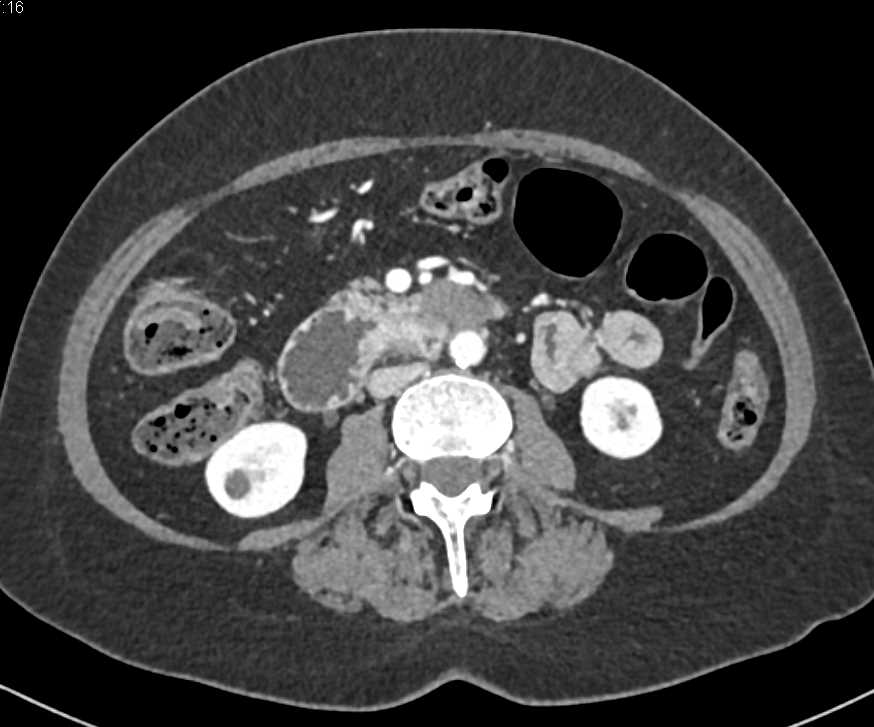

Duodenal Carcinoma with Obstruction